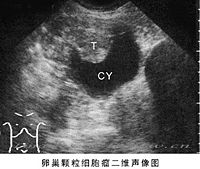

为最常见的一种具有内分泌(以雌激素为主)功能的卵巢肿瘤。占全部卵巢肿瘤的1~2%。可发生于任何年龄,据上海医科大学等统计,平均发病年龄为52岁,60%在绝经期后,青春期前者<5%。图示右卵巢区囊实性肿块,囊壁附有乳头状实质性回声团块。T=肿块;CY=囊液。